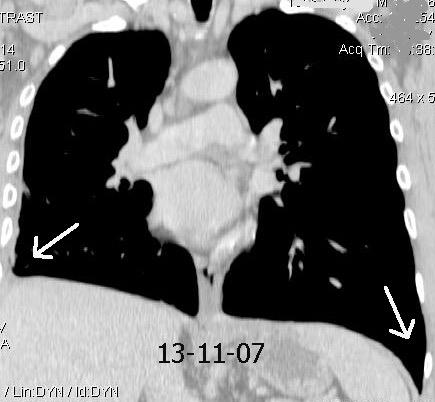

87. NEUMOTÓRAX ESPONTÁNEO

89. NEUMOTÓRAX. SÍNDROMES POROSOS

90. NEUMOTÓRAX A TENSIÓN

91. NEUMOTÓRAX EN ESPIRACIÓN

92. PLACAS PLEURALES

94. QUILOTÓRAX

95.QUISTE HIDATÍDICO PLEURAL

96. SARCOMA SINOVIAL

97. SURCO PROFUNDO , SIGNO DE